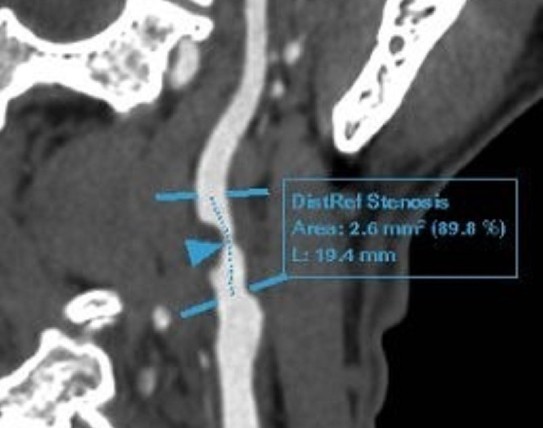

| Phim chụp tổn thương của bệnh nhân. |

Các kết quả siêu âm và chụp cắt lớp mạch máu não cho thấy ông Đ. bị hẹp nặng 90% gốc động mạch cảnh trong phải do mảng xơ vữa hỗn hợp, kèm theo lóc tách nhỏ gốc động mạch cảnh trong trái với núm phình nhỏ. Mảng xơ vữa cũng lan tỏa ở nhiều đoạn mạch khác như động mạch dưới đòn và xoang hang. Chụp CT động mạch vành ghi nhận xơ vữa vôi hóa nhẹ, gây hẹp 30-40% các nhánh động mạch vành.